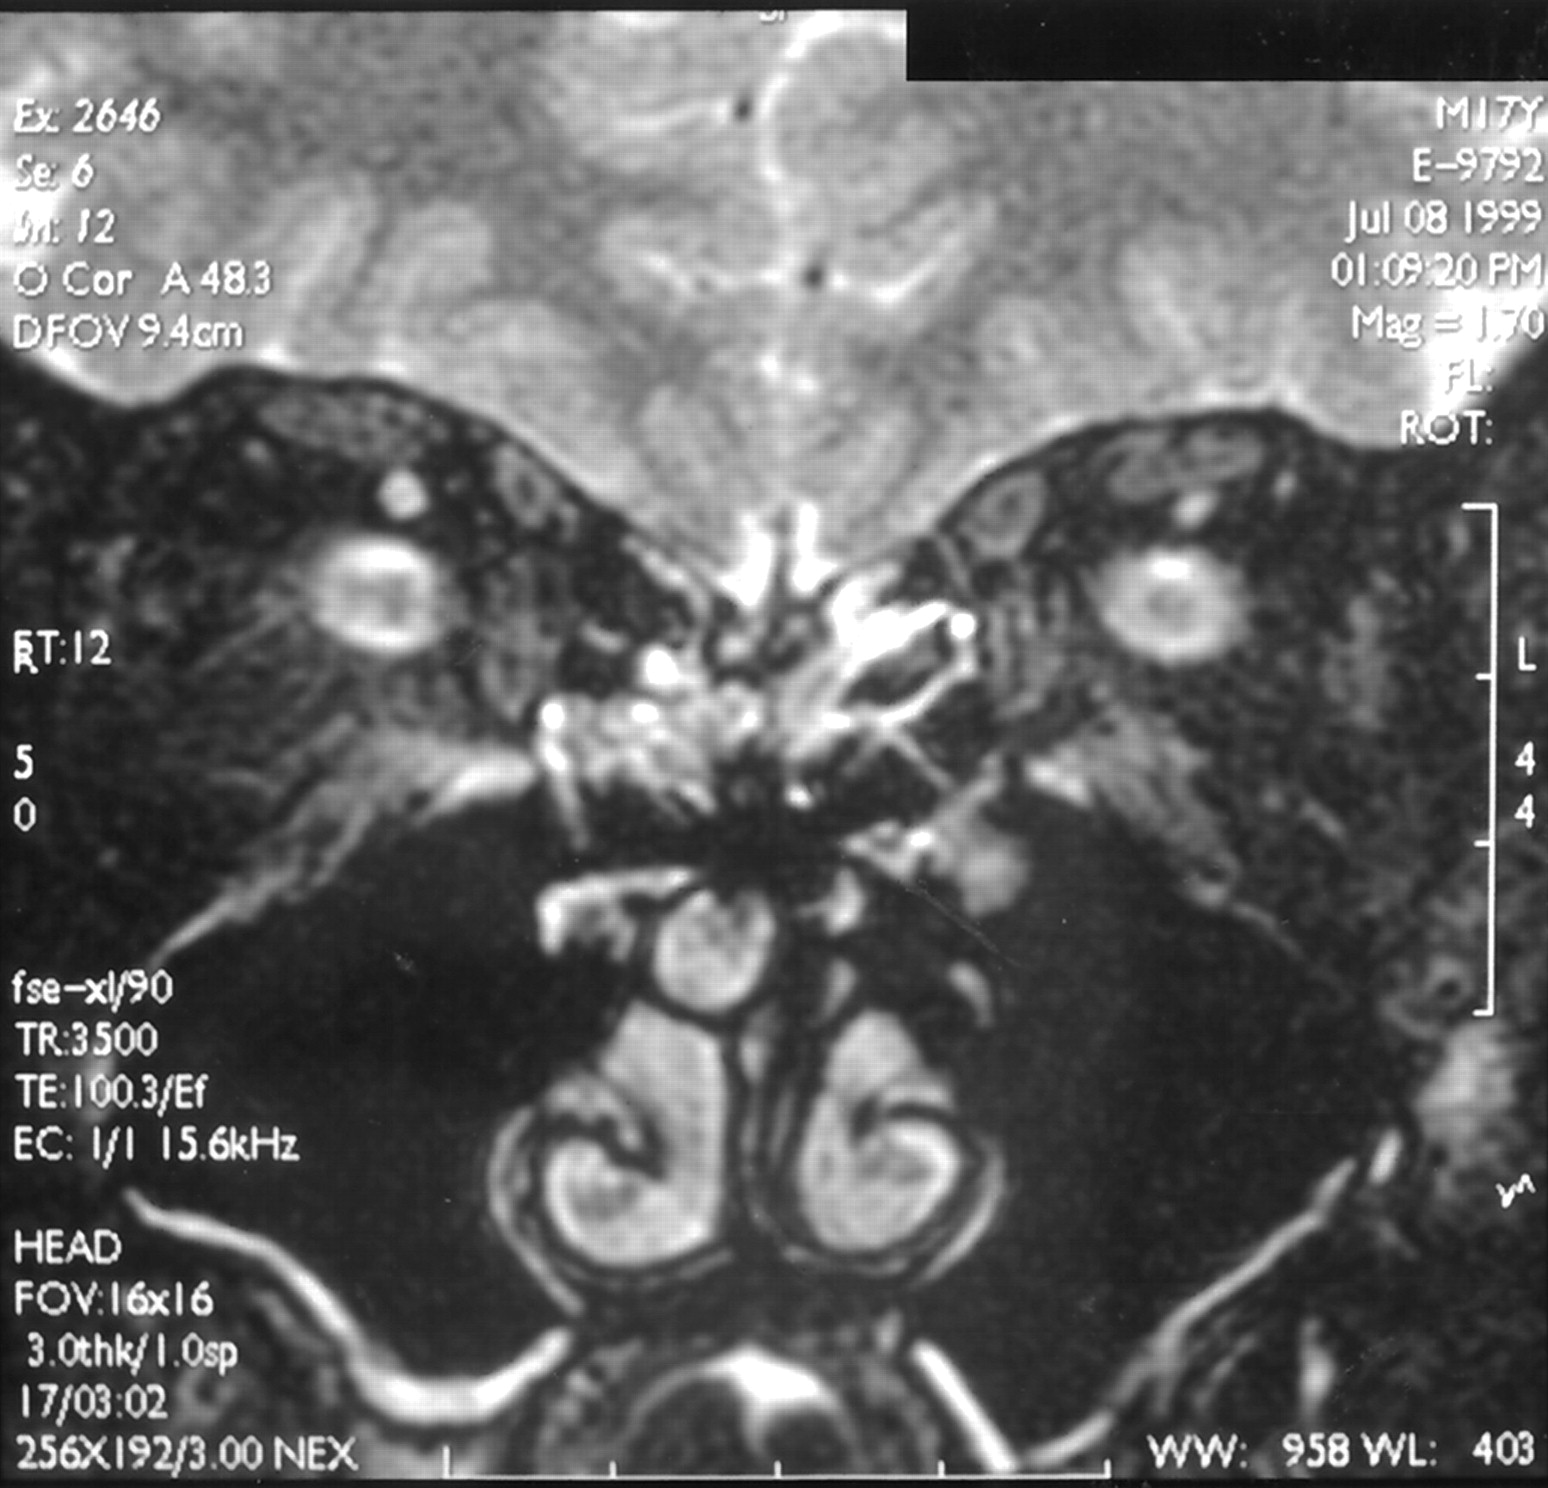

轨道轴向和冠状扫描显示没有区别在眶视神经升高或双方之间的神经鞘的大小(图2)。受影响方从未超过0.5毫米,和所有情况下的平均差是0.2毫米(SD, 0.25毫米)。在midorbital层面,视神经/鞘复杂的直径是5.0毫米(SD, 0.6),对所有轨道。10例MRI中,没有显示静脉窦畸形。